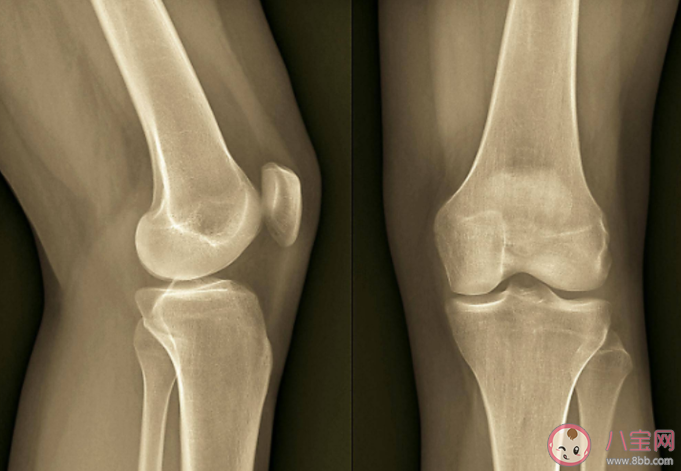

随着年龄增大,很多老人会出现关节炎问题,空调不是病因,但「冷」可能会加重疼痛感。

有肩周炎、老寒腿等关节不好的人,长时间在低温的空调房间,比如10~17摄氏度,身体里面TRPA1通道开启,而这种通道的激活在炎症的疼痛中很重要。